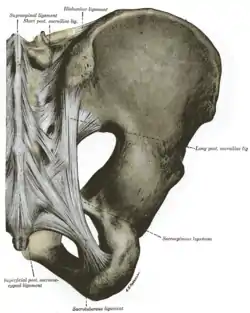

Articulations of pelvis. Anterior view. Articulations of pelvis. Posterior view.

Articulations of pelvis. Posterior view. Low-dose CT scan of sagittal pelvic outlet diameter as part of pelvimetry